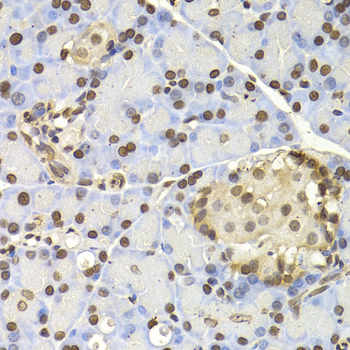

Immunohistochemistry of paraffin-embedded human tonsil tissue using NAP1L1 antibody.

• A2769: image 3

Immunohistochemistry of paraffin-embedded rat pancreas using NAP1L1 antibody at dilution of 1:200 (400x lens).